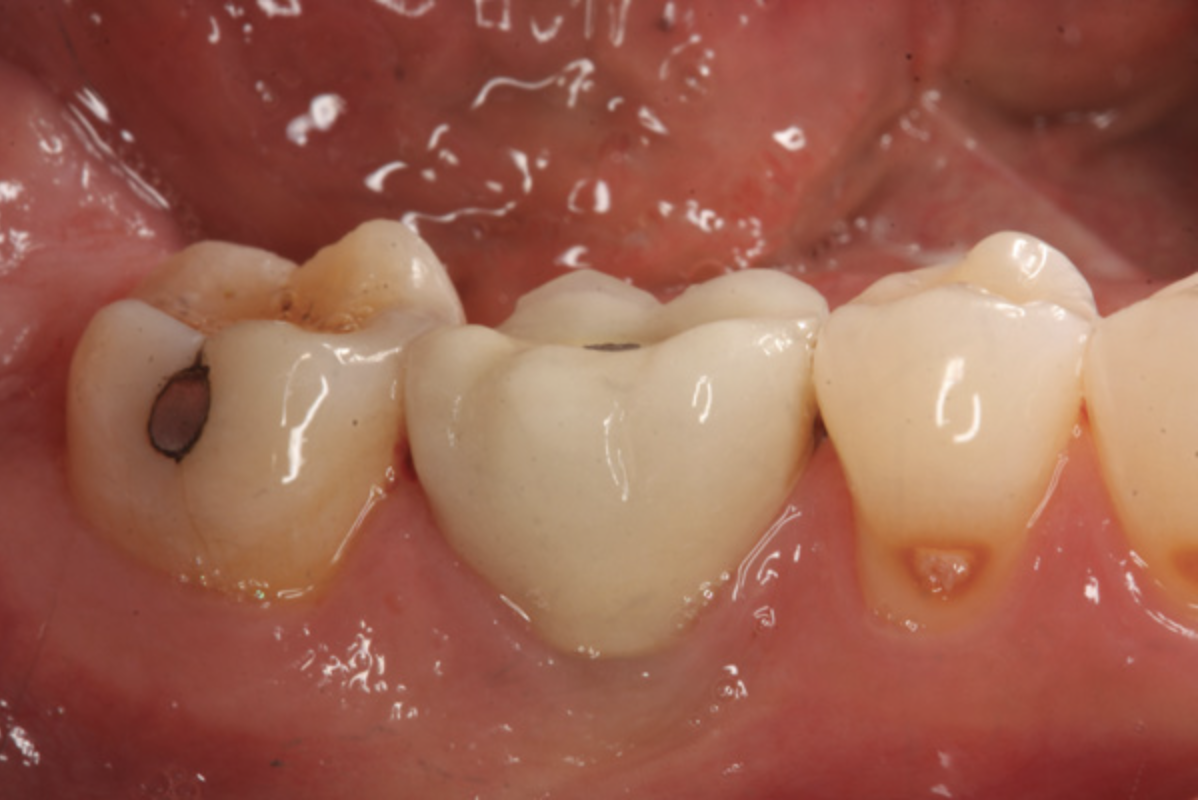

Fig 4. Pure-phase ß-TCP covered with a collagen barrier.

Figure 4

There are concerns that graft materials that fully resorb in a short timeframe may contribute to site collapse. Pure-phase beta-tricalcium phosphate (ß-TCP) (Figure 4) was one of the materials developed to address this concern. In a clinical and histologic study, extraction sockets were shown to have 91% of ridge width preserved when grafted with ß-TCP (Cerasorb®, Curasan, Inc., www.curasaninc.com) and covered with either a collagen or dense PTFE barrier.7 Dental implants were placed in these patients at 4 to 6 months postoperatively, a later time period than in the calcium sulfate studies. The patient shown in Figure 4 had only three maxillary teeth remaining, supporting an ill-fitting removable prosthesis. Due to the significant occlusal forces that were to be demanded on this single-tooth, implant-supported restoration, it was deemed advantageous to maximize the amount of vital bone in the recipient site. The area was left to heal for 7 months before flap exposure (Figure 5), implant placement in an ideal location, and graft analysis in the largest part of the defect. Analysis of the retrieved specimen showed 85% vital bone in the apical 90% of the core and a thin layer of nonresorbed ß-TCP at the crestal portion (Figure 6).